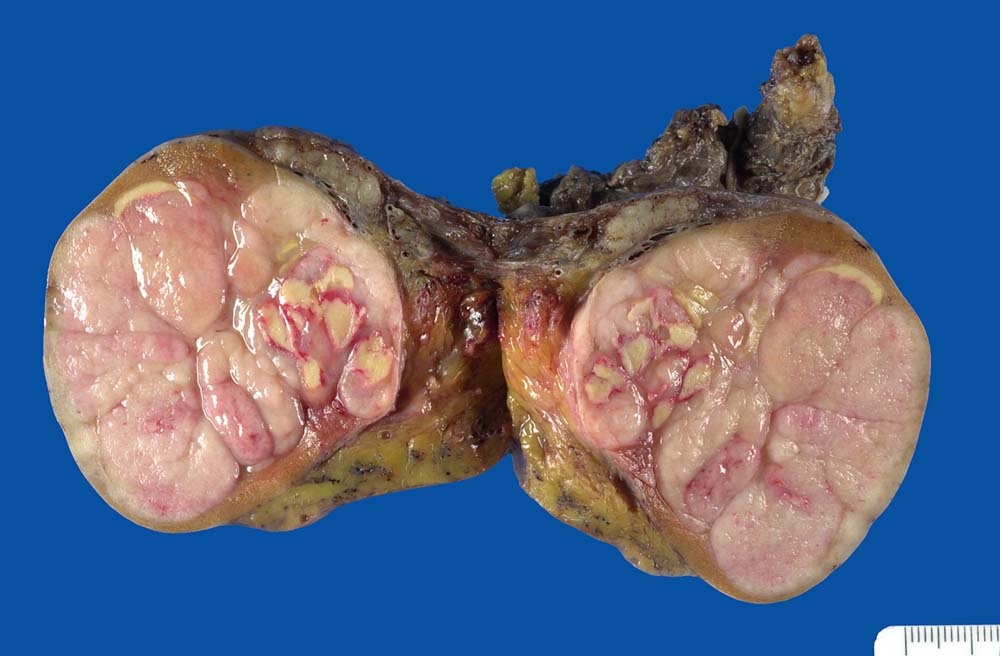

PathoPic ID 9153 - Klassisches Seminom des Hodens

Klassisches Seminom des Hodens

maligner Tumor

Hoden

Genitalorgane, männlich

Beiger lobulierter fleischiger Tumor mit herdförmigen hellgelben

Nekrosen mit hämorrhagischem Randsaum.

Hodentumor

Makroskopie

31

männlich